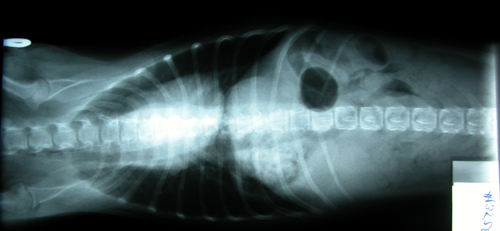

I got a hiatal hernia.  See my stomach is supposed to be all to the right side of my diaphram, but my diaphram didn't develop right, and my stomach and part of my spleen were slipping in and out of my chest cavity.  I had really bad heartburn all the time I was a puppy, but I couldn't tell anybody about it.  All my humans just thought I was moody.

See the big black dot?  That's a stink-bomb I'll let loose later, preferably in a small, closed space!